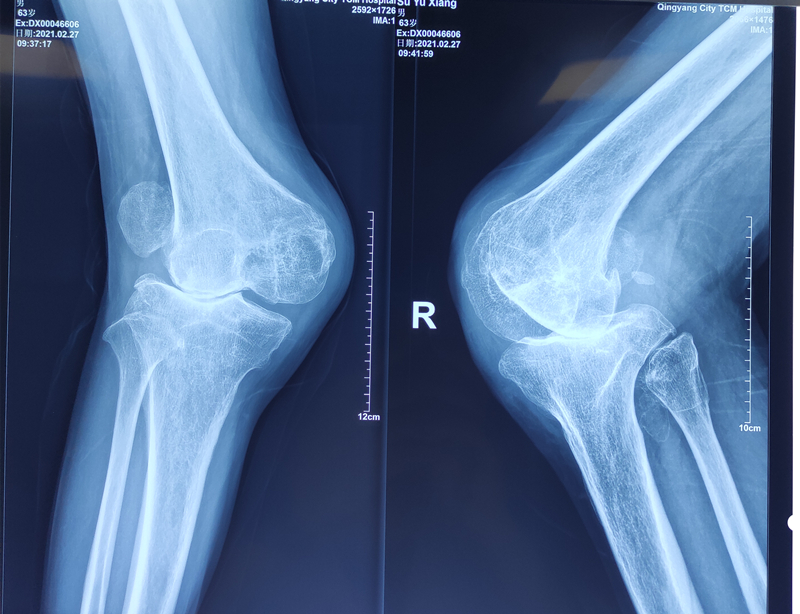

我院骨伤二科李崇鑫副主任医师成功完成一例双侧膝关节重度外翻人工膝关节置换术。

患者苏某,男,63岁,17岁时双膝关节被土方塌伤,当时由于条件有限,未及时治疗。现如今畸形严重,必须依靠双拐支撑走路,并且呈逐渐加重趋势,多处求医无果。经打听,找到我院骨二科李崇鑫副主任医师。

入院诊断为双侧膝关节外翻畸形(重度),双侧髌骨陈旧性脱位,双侧膝关节屈曲挛缩畸形。由于患者年龄偏大,病情严重,手术技术要求高,难度及风险极大,一旦失误,将会带来灾难性的后果。李崇鑫副主任医师积极准备手术,详细制订手术方案,于3月16日下午顺利完成右侧人工膝关节置换手术。术程顺利,术后外翻畸形完全纠正,恢复正常力线,髌骨轨迹完全纠正。